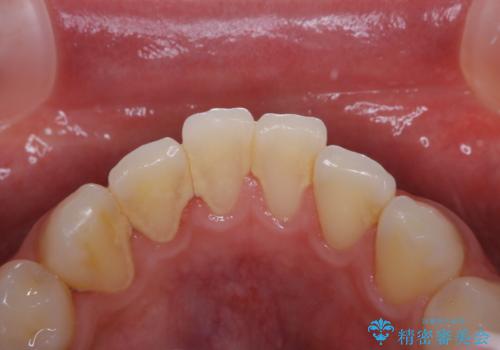

茶渋による着色と下の前歯の裏側のべったり歯石

担当医 歯科衛生士